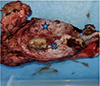

![]() |

Figure 1 Gross image of the tumour showing the ulceroproliferative tumour involving buccal Mucosa (blue star), lower gingivobuccal sulcus (blue cross) and mandible (blue arrow). |